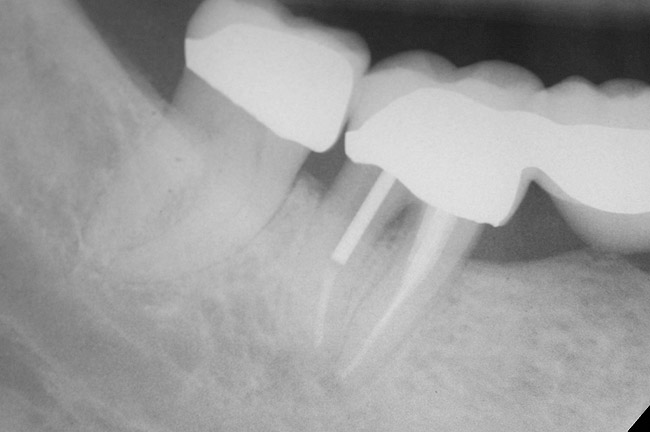

The clinician also must consider the status of the adjacent teeth. Figure 6 shows teeth Nos. 29 and 31 prepared for a fixed bridge. Factors to be considered in this example were the short root of tooth No. 29 with a distal biologic width violation and a short root trunk on tooth No. 31 (which leads to furcation involvement with a small amount of facial or lingual bone loss). This patient also had periodontal disease, which further decreased the long-term prognosis of the fixed bridge option. No prospective studies directly compare the longevity of the two options: a three-unit fixed bridge vs an implant.37 Other factors that complicate comparisons of an implant vs a fixed three-unit bridge are the variability of fixed bridges as well as the variability of the implants (amount of bone, implant length, etc). For example, endodontically treated abutment teeth do not last as long as nonendodontically treated abutment teeth.38 Restorations on teeth with endodontic posts and a minimal length of ferrule do not persist as long as those on teeth without a post and at least a 2-mm ferrule.39

Figure 6   Tooth No. 29 with the temporary build-up close to the osseous crest. Tooth No. 29 has a short post, and tooth No. 31 has a very short root trunk.

Figure 6